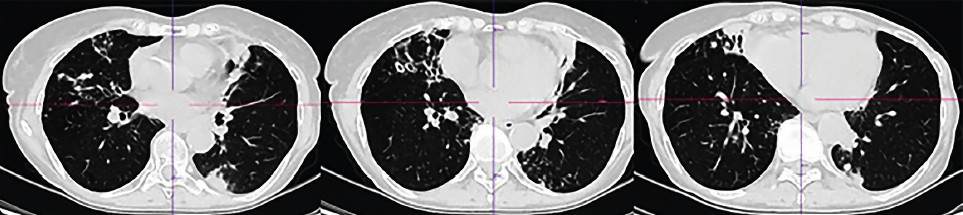

CT scans of the chest organs were performed repeatedly, where various dynamics were noted: migration of compaction areas, changes in their size and shape, changes in the shape and number of dilated bronchi. In general, the dynamics are negative, with a slow increase in the severity of bronchiectasis, the number and size of compaction areas (Table 1, Fig. 1–3).

Fig.1. Computed tomography of the chest organs of patient R dated 09/02/2022